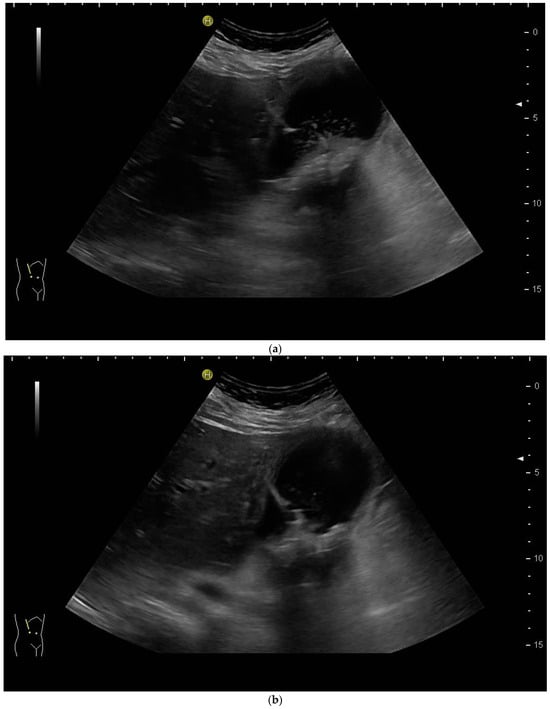

PTBD is commonly performed in the so-called “in plane technique” (Figure 1a,b).

Figure 1.

(a) Puncture in plane. The needle is inserted at the centre of the small side of the transducer; (b) Needle tip (yellow arrow), body (white arrows), and target (bile duct) are depicted in one plane. The needle tip is kept in plane by very small movements of the transducer.

The needle is inserted at the narrow side of the transducer and advanced in the US plane. It can thereby be depicted on its whole trajectory. For a successful puncture, the interventionalist has to keep the needle shaft, tip, and target (bile duct) on the image at all times. Losing the tip or the target being out of sight will obviously prohibit a successful puncture. Not having the needle shaft in sight but seeing the tip and target means the further trajectory of the needle will miss the bile duct. Careful tiny corrections, either of the probe orientation or needle direction, must then be undertaken to have all three in sight during the procedure.

However, the “free hand” technique allows for every puncture angle and is, therefore, preferred by us. The use of colour Doppler will enable the doctor to avoid blood vessels and identify smaller bile ducts (Figure 3a,b).

Figure 3.

(a) Hypoechoic tubular structures in Segment V are visualised in an intercostal view; (b) Colour Doppler helps to differentiate between bile ducts and blood vessels.

In cases of extrahepatic obstruction, mostly the right liver lobe will be addressed. It is common practice to head for the peripheral branches in Segment V (cf. Figure 3a,b), as from there to the common bile duct, the biliary branches form a harmonic arch, and the forward movement of the guide wire seems unpretentious [3]. However, US guidance allows the puncture of any biliary duct of the right or left liver lobe that can be depicted well (Figure 4a–c).